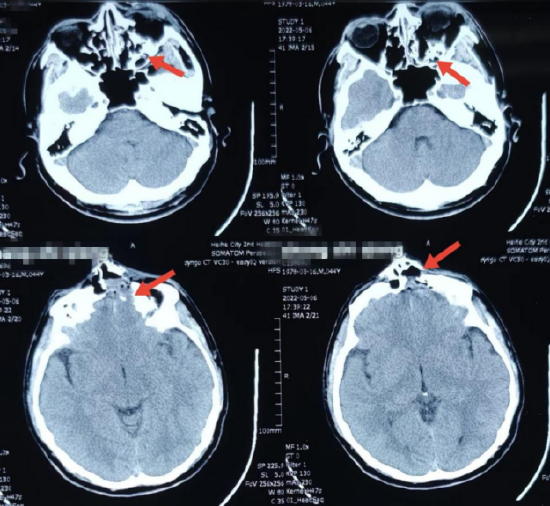

右额部硬膜外血肿;2. 右额部及眼眶颅骨粉碎性骨折;1.